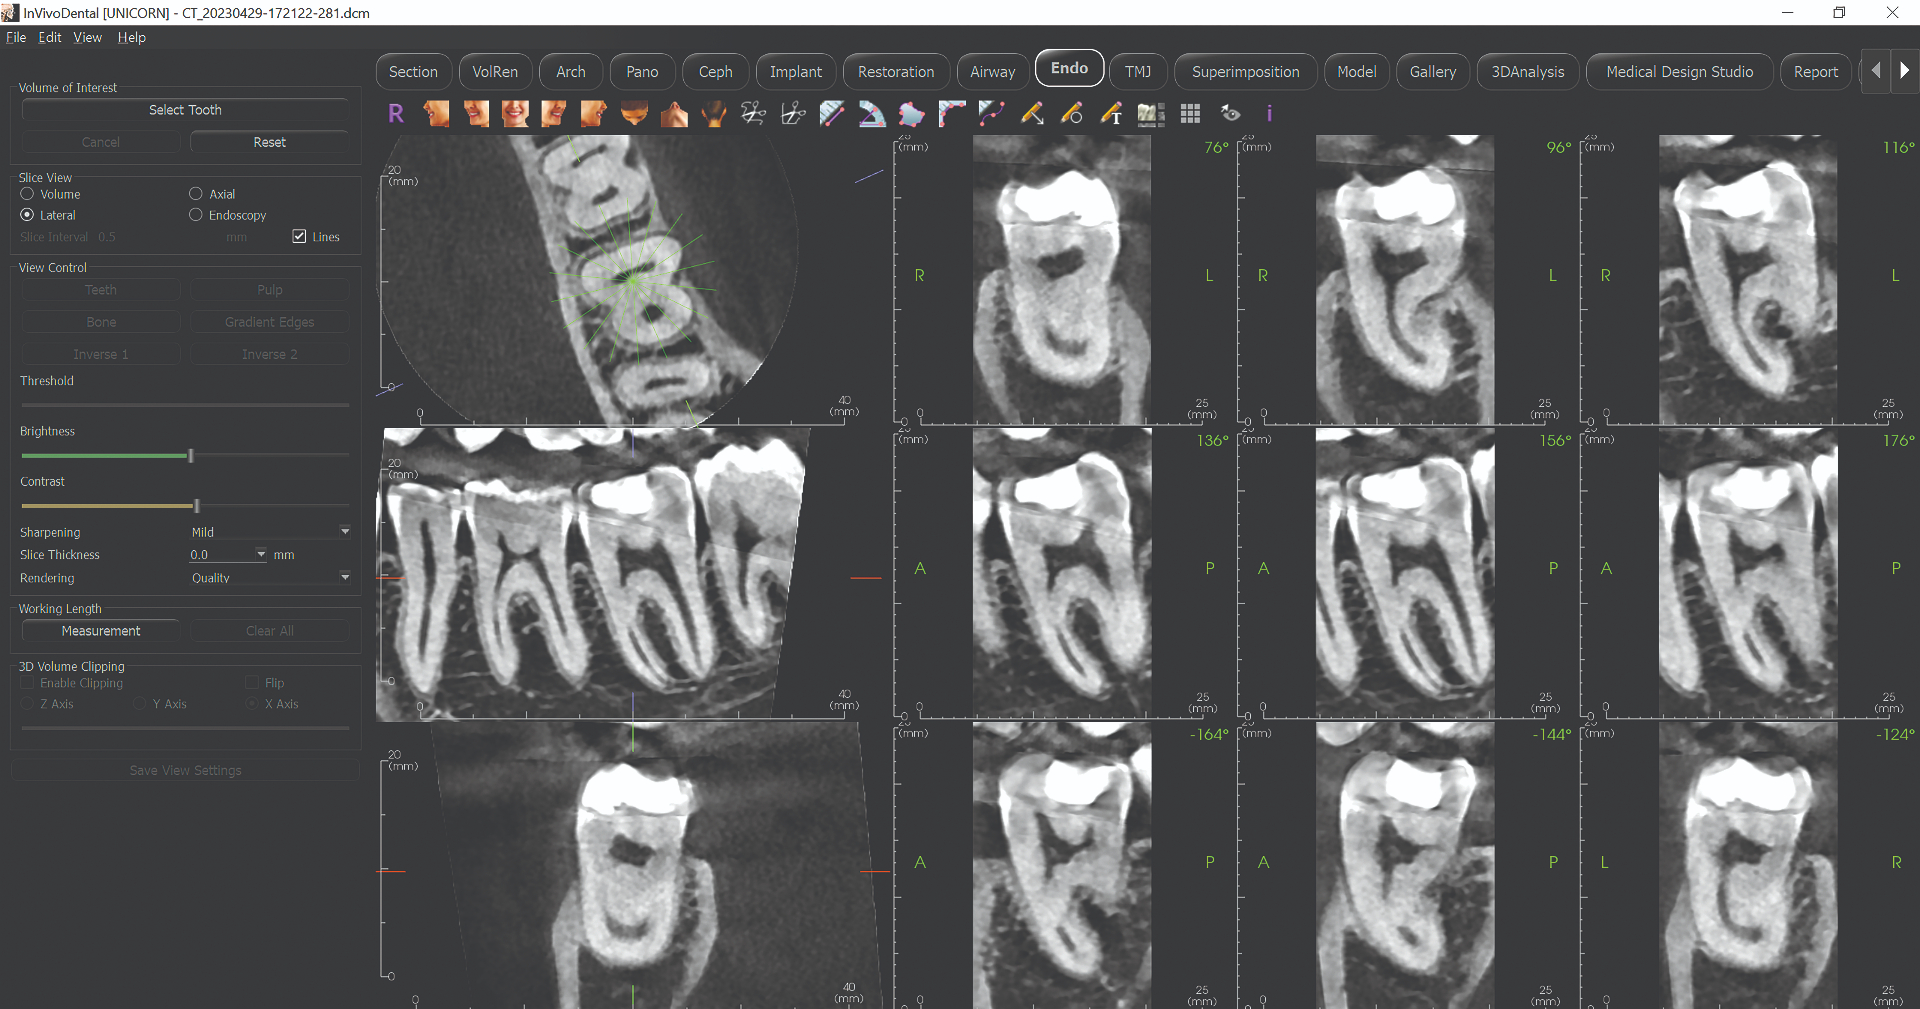

Master CBCT Implant Planning

Learn to plan dental implants with precision & confidence using CBCT imaging

A comprehensive live online masterclass for dentists looking to enhance their implant success rates

⚠️ Note: This is Part 1 & 2 of our comprehensive CBCT course. Complete curriculum will be provided by Dr. Aarti Singh.